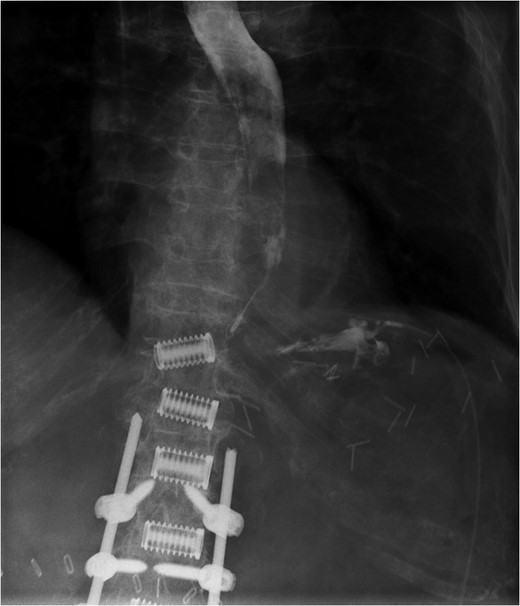

A 69-year-old woman who was previously well, with no history of steroid or non-steroidal anti-inflammatory use, was referred to our unit with an iatrogenic oesophageal perforation. She had undergone a laparoscopic cholecystectomy 5 weeks earlier, complicated by a secondary intra-abdominal bleed requiring laparotomy and splenectomy. The post-operative period was further complicated by small bowel obstruction secondary to internal herniation. This required an emergency laparotomy during which a posterior gastric perforation was identified (Fig. 1). Prior to transfer to our unit, the patient had undergone an upper GI endoscopy and attempted endoscopic placement of a VAC therapy device in order to treat this gastric perforation. Whilst attempting to progress the sponge component of the VAC device, the patient suffered an iatrogenic oesophageal injury. Computed tomography (CT) imaging demonstrated mediastinal emphysema, confirming a full thickness tear of the cervical oesophagus (Fig. 2).

Fluoroscopic image demonstrating contrast entering intraperitoneal drain in proximity to gastric perforation (previous spinal surgery).